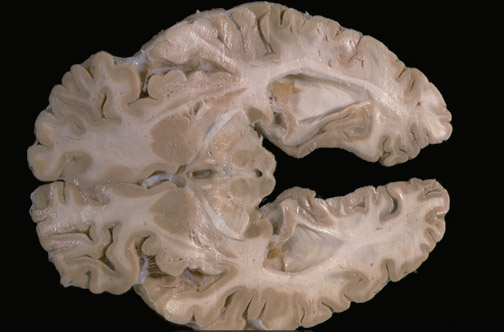

Identify the following regions of the brain on transverse section by clicking in the image below:

Third Ventricle - Red Nucleus - Fornix - Optic Tract - Caudate & Putamen - Lateral Geniculate Nucleus - Superior Colliculus